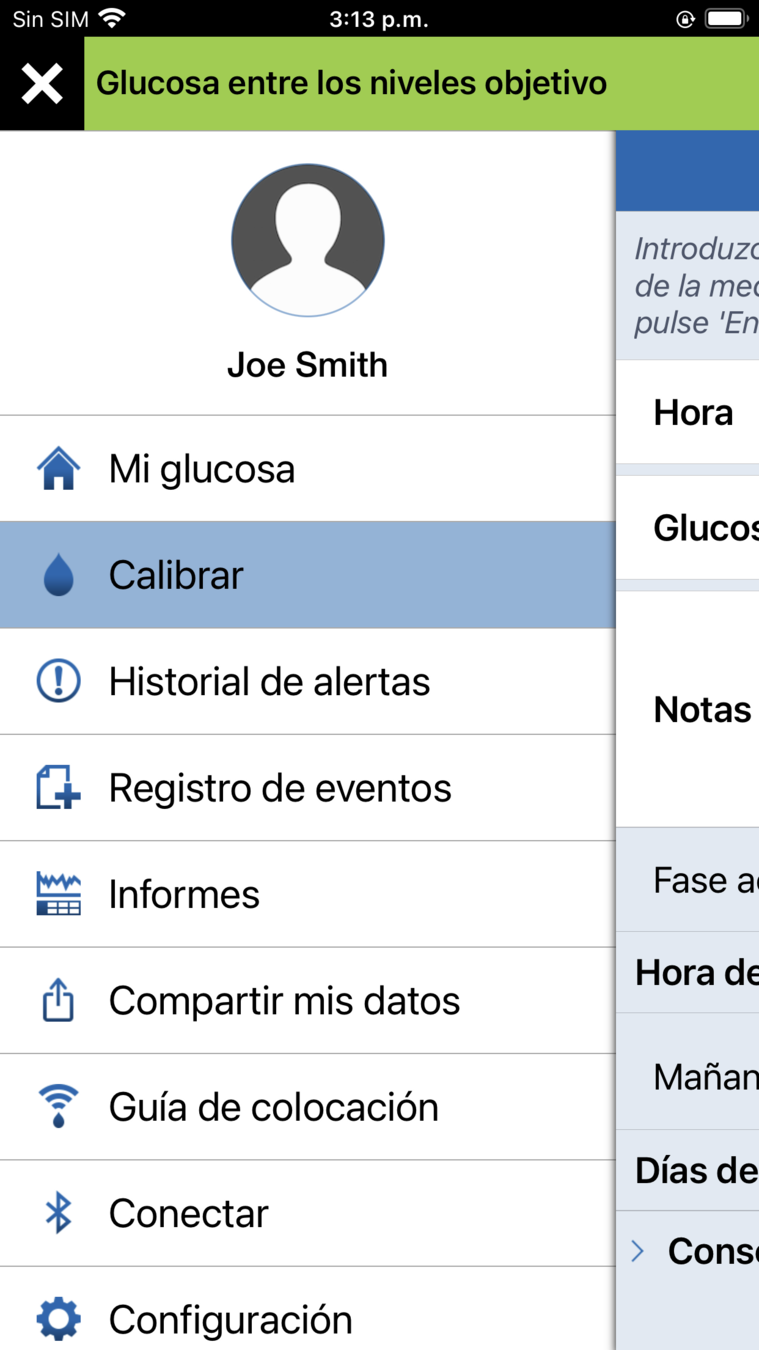

Para ir a su configuración personalizada, toque el icono de menú para abrir el Menú Principal.

ACCEDA A LA CONFIGURACIÓN PERSONALIZADA

Desplácese hacia abajo y toque Configuración.

Para ir a su configuración personalizada, toque el icono de menú para abrir el Menú Principal.

A continuación, toque Glucosa.

Desplácese hacia abajo y toque Configuración.

Para ir a su configuración personalizada, toque el icono de menú para abrir el Menú Principal.

PANTALLA CALIBRAR

Si se desplaza a la pantalla Calibrar desde

el menú principal, puede comprobar

PANTALLA CALIBRAR

- en qué fase de calibración diaria se encuentra;

Si se desplaza a la pantalla Calibrar desde

el menú principal, puede comprobar

lo siguiente:

- cuándo hay que realizar la próxima calibración.

Pantalla Calibrar

- en qué fase de calibración diaria se encuentra;

Si se desplaza a la pantalla Calibrar desde

el menú principal, puede comprobar

lo siguiente:

Si le resulta más cómodo según su día, tiene la opción de calibrar antes, es decir, antes de recibir la alerta de que hay que efectuar una calibración.

- cuándo hay que realizar la próxima calibración.

- en qué fase de calibración diaria se encuentra;

Si se desplaza a la pantalla Calibrar desde

el menú principal, puede comprobar

lo siguiente: